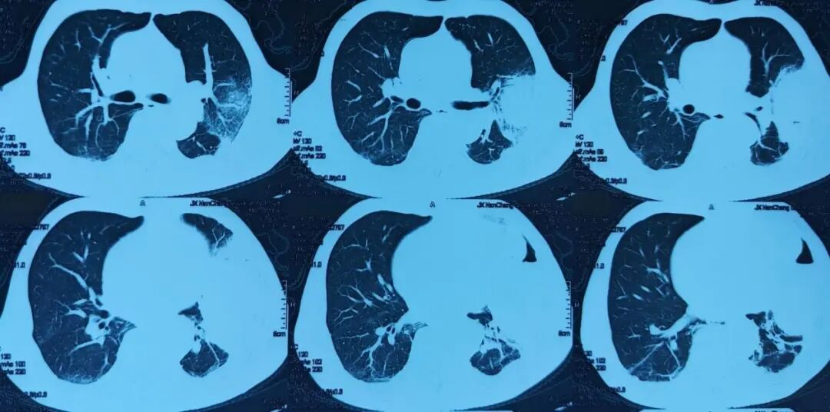

现病史:患者1个月前参加酒席后出现咳嗽、咳脓痰,伴畏寒发热,体温38度,于当地市人民医院就诊,2026年1月19日行胸部CT检查示:两肺感染可能,双肺多发小、微结节,心包、左侧胸腔少量积液(图片1)。予左氧氟沙星输液治疗,仍有发热伴咳嗽咳痰,间断有少量痰血,再次就诊于当地市人民医院,2026年1月31日行气管镜检查,灌洗液mNGS提示:惠普尔养障体 序列数283,小孢根霉 序列数66,建议患者至省会医院进一步就诊。2026年2月5日患者于当地省会医院住院,予静脉输注艾沙康唑抗真菌治疗,2026年2月9日行胸部增强CT检查示:左上胸膜下大片状高密度影伴明显坏死、积气,结合临床符合毛霉病并胸膜侵犯,双侧胸腔少量积液,左侧部分包裹性改变(图片2)。因患者病灶较前增大,病情进展,家属要求转院至上海治疗。

图片1:2026年1月19日当地市人民医院胸部CT示两肺感染可能,双肺多发小、微结节,心包、左侧胸腔少量积液。